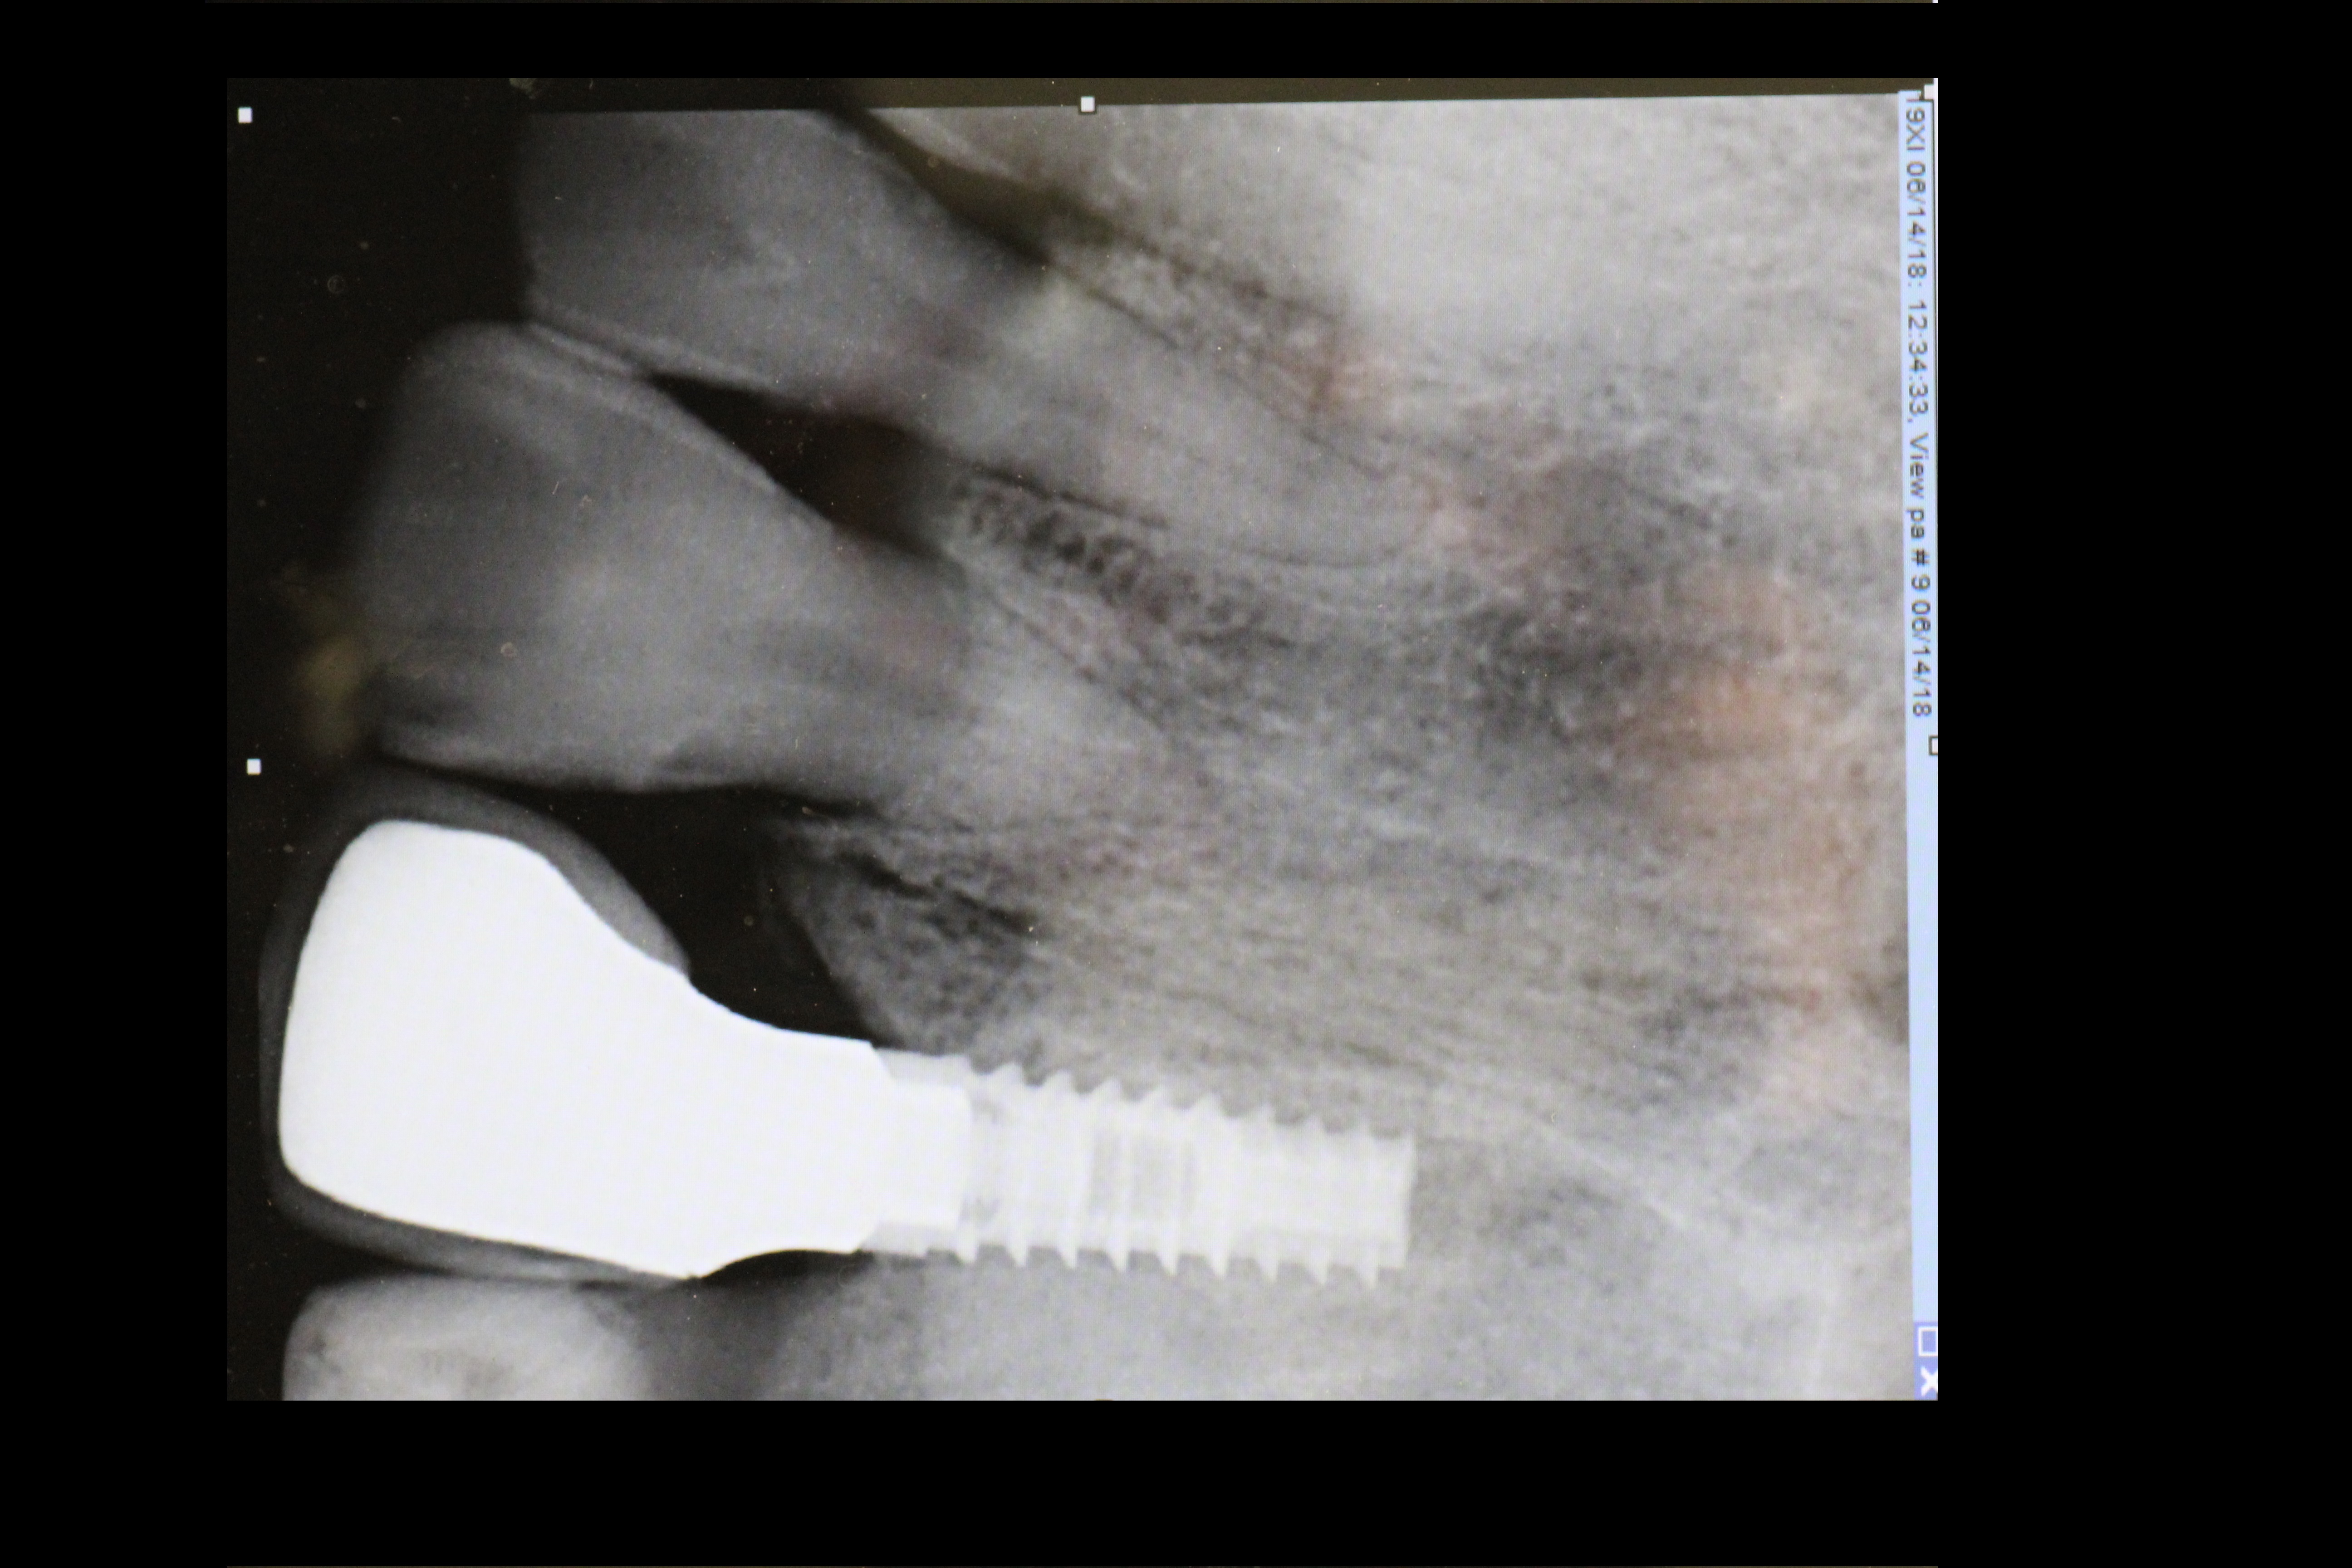

- Implant is in place.

-

- Bony defect measuring 3mm x 10 mm.